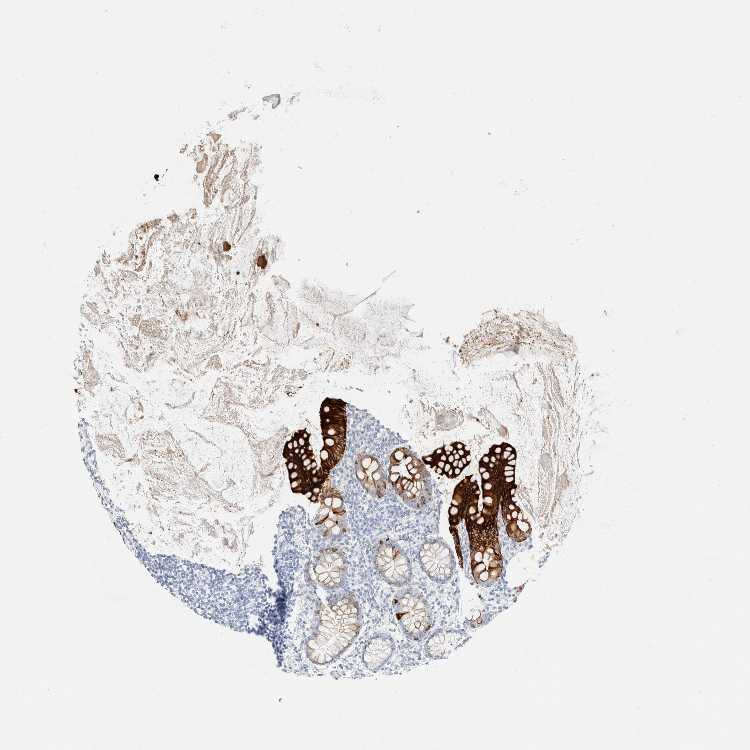

APPENDIX - Expression summary

Protein expression

Appendixi

On the top, protein expression in current human tissue, based on all annotated cell types, is reported with the units not detected (n), low (l), medium (m) and high (h). Underneath, protein expression in each annotated cell type are reported using the same units.

Protein expression data is based on knowledge-based annotation. For genes where more than one antibody has been used, a collective score is set.

APPENDIX - Antibody stainingi

Antibody staining in the annotated cell types in the current human tissue is reported as not detected, low, medium, or high, based on conventional immunohistochemistry profiling in selected tissues. This score is based on the combination of the staining intensity and fraction of stained cells.

Each image is clickable and will lead to virtual microscopy that enables deeper exploration of all samples and also displays staining intensity scores, fraction scores and subcellular localization as well as patient and tissue information for each sample.

Antibody HPA024309Antibody HPA024684Antibody HPA027236Antibody CAB000032

Endocrine cells ---High

Enterocytes ---High

Enterocytes - Gradient ---Ascending

Enterocytes - Microvilli ---High

Germinal center cells ---Not detected

Glandular cells HighHighHigh-

Goblet cells ---High

Lymphoid tissue -Not detectedNot detected-

Non-germinal center cells ---Not detected